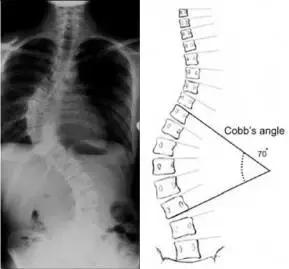

Cobb’s角

医学上用于判断脊柱侧弯严重程度常用Cobb’s角,通过X线观察到偏离水平位置最多的椎体,沿着椎体画两切线,这两条线形成的夹角就是Cobb角。度数超过10度则为脊柱侧凸,度数越大则脊柱侧弯越严重。